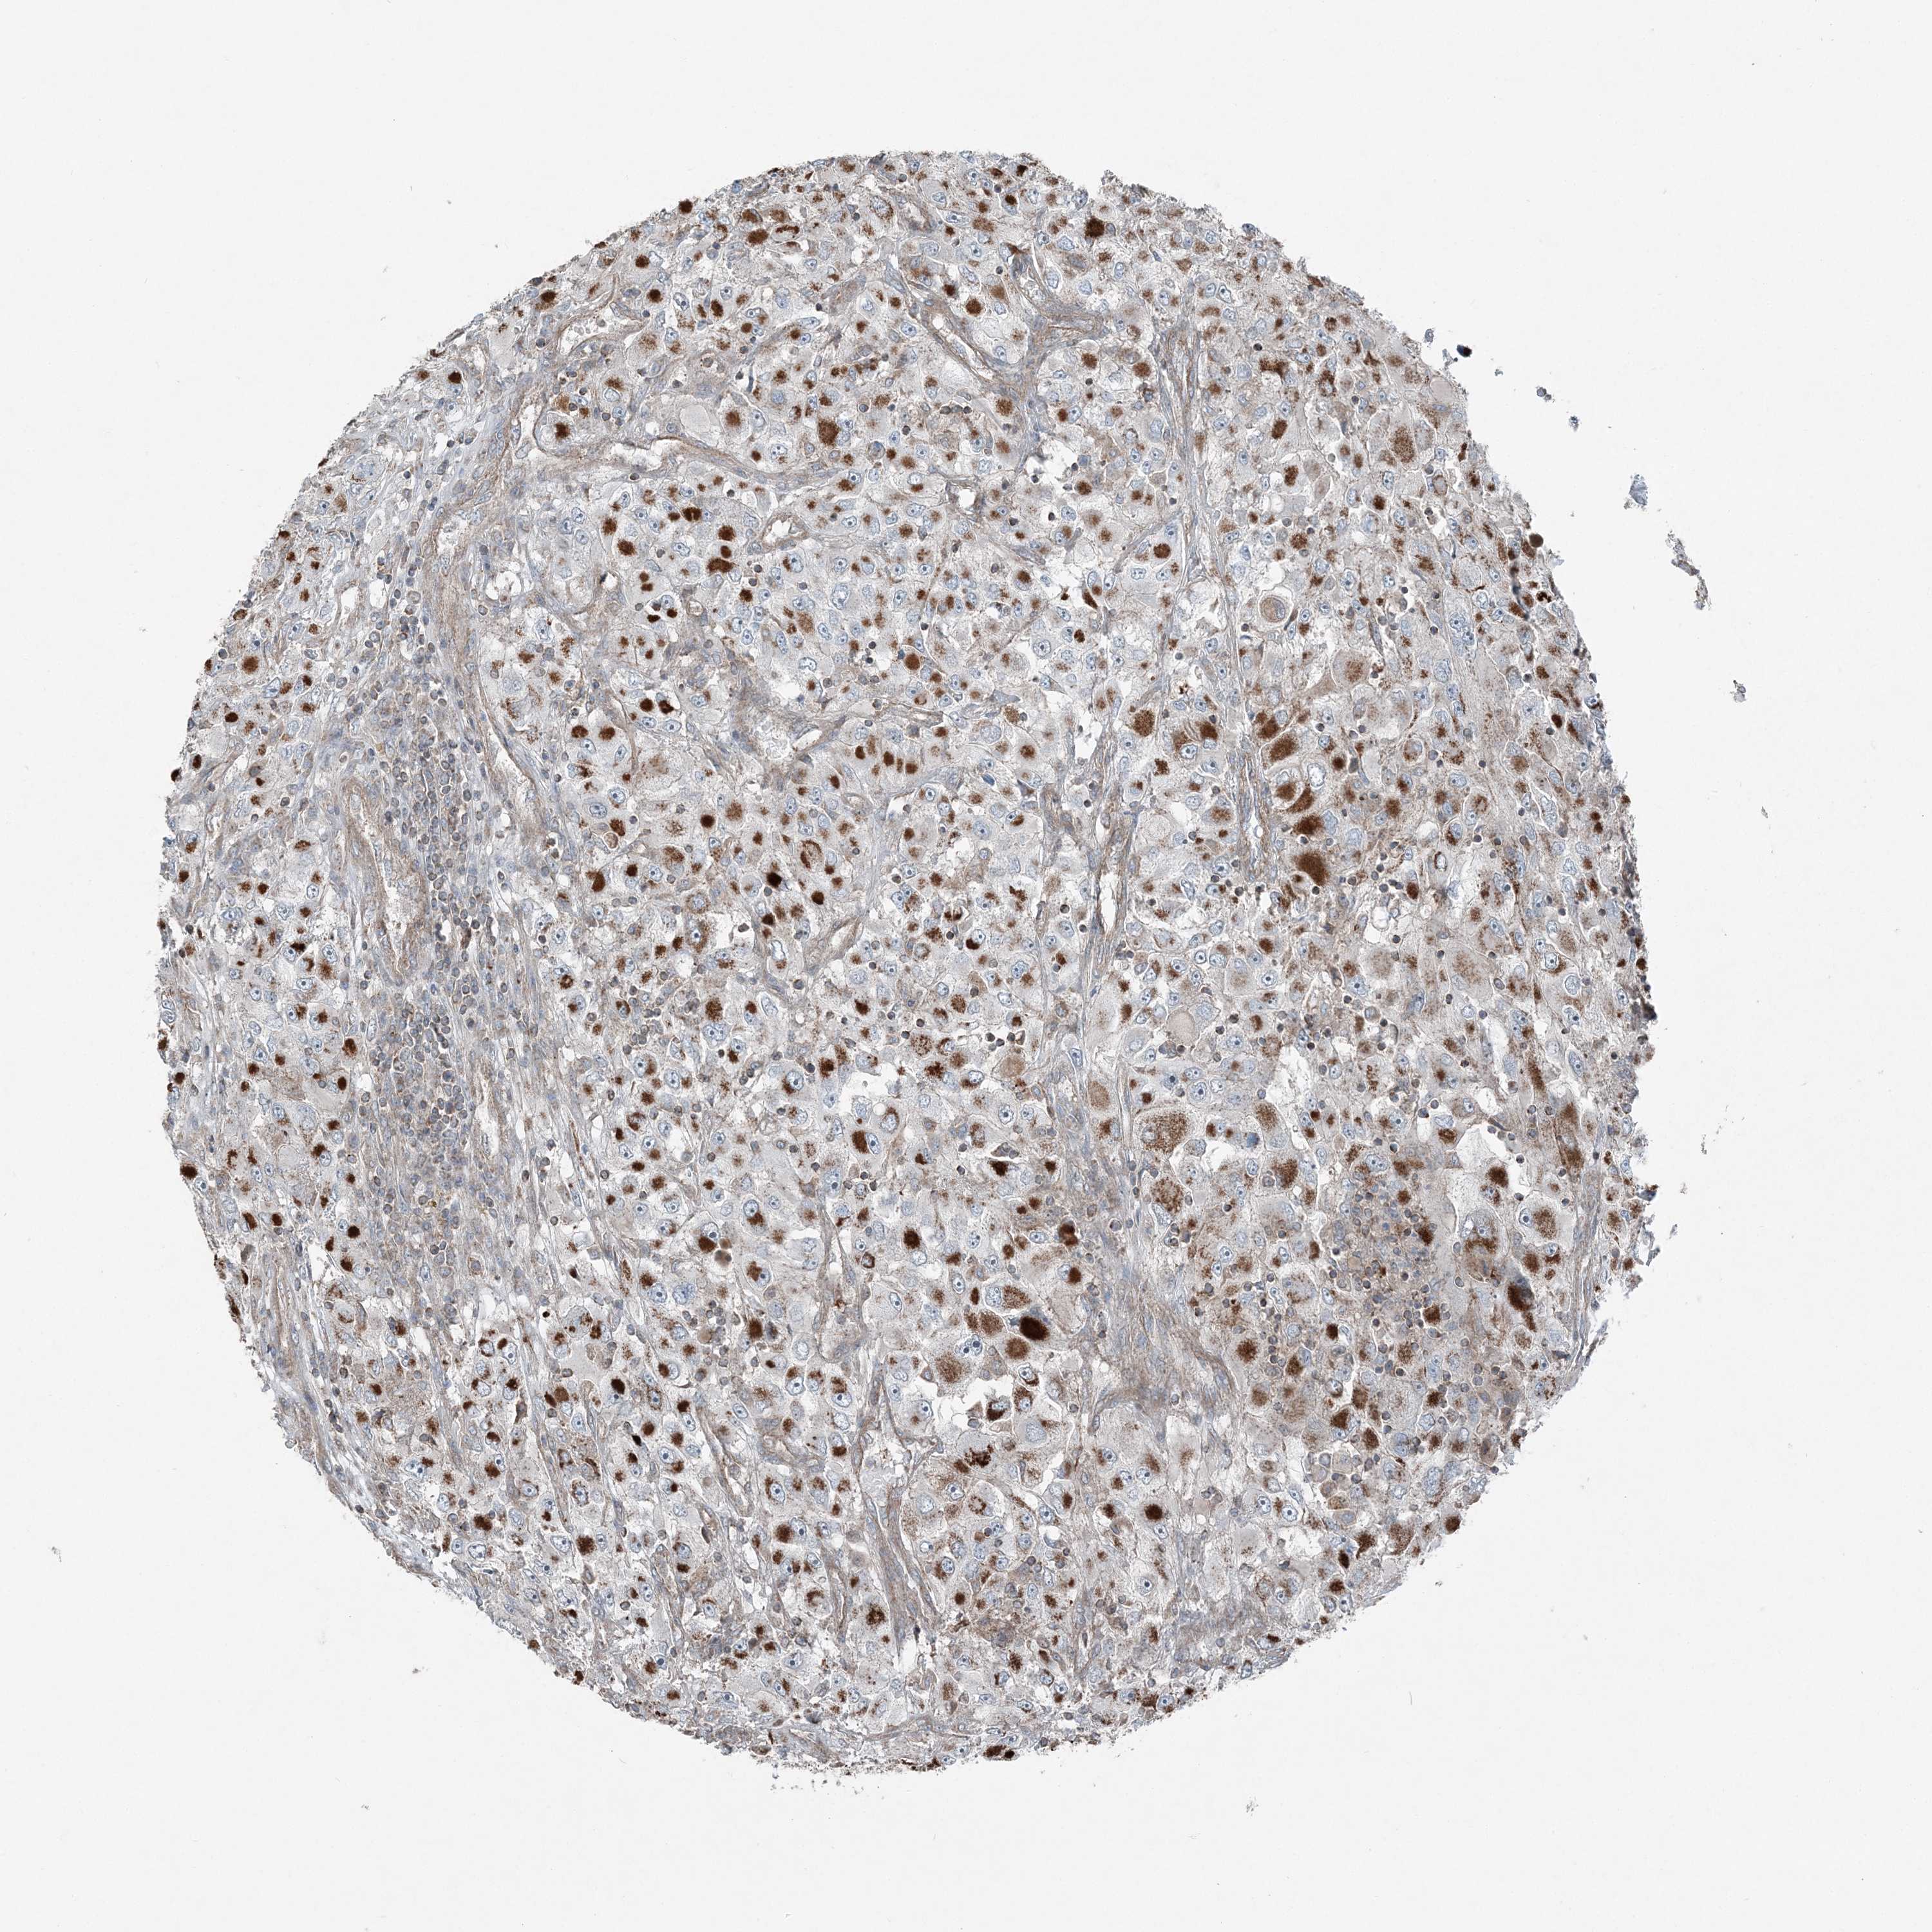

KIDNEY RENAL CLEAR CELL CARCINOMA (VALIDATION) - Interactive survival scatter ploti

The Survival Scatter plot shows the clinical status (i.e. dead or alive) for all individuals in the patient cohort, based on the same data that underlies the corresponding Kaplan-Meier plots. Patients that are alive at last time for follow-up are shown in blue and patients who have died during the study are shown in red.

The x-axis shows the expression levels (FPKM) of the investigated gene in the tumor tissue at the time of diagnosis. The y-axis shows the follow-up time after diagnosis (years). Both axes are complimented with kernel density curves demonstrating the data density over the axes. The top density plot shows the expression levels (FPKM) distribution among dead (red) and alive patients (blue). The right density plot shows the data density of the survived years of dead patients with high and low expression levels respectively, stratified using the cutoff indicated by the vertical dashed line through the Survival Scatter plot. This cutoff is automatically defined based on the FPKM cutoff that minimizes the p-score. The cutoff can be changed by dragging the vertical line or by entering a cutoff value in the square labeled "Current cut-off".

Under the Survival Scatter plot the p-score landscape (black curve; left axis) is shown together with dead median separation (red curve; right axis). Dead median separation is the difference in median mRNA expression between patients who have died with high and low expression, respectively. It is calculated as follows: median FPKM expression of dead patients with high expression - median FPKM expression of dead patients with low expression. This is intended to aid the user in visually exploring custom cutoffs and the associated p-scores and dead median separation.

Individual patient data is displayed and can be filtered by clicking on one or more of the category buttons on the top of the page. Categories describing expression level and patient information include: high, low, alive, dead, female, male and tumor stages. The scale of the x-axis can be toggled between linear and log-scale by clicking on the "x log" button. Mouse-over function shows TCGA ID, patient information and mRNA expression (FPKM) for each patient.

& Survival analysisi

Kaplan-Meier plots summarize results from analysis of correlation between mRNA expression level and patient survival. Patients were divided based on level of expression into one of the two groups "low" (under cut off) or "high" (over cut off). X-axis shows time for survival (years) and y-axis shows the probability of survival, where 1.0 corresponds to 100 percent.

KY is not prognostic in Kidney Renal Clear Cell Carcinoma (validation)

TCGA RNA samplesi

RNA-seq data is reported as average FPKM (number Fragments Per Kilobase of exon per Million reads), generated by the The Cancer Genome Atlas (TCGA) .

Normal distribution across the dataset is visualized with box plots, shown as median and 25th and 75th percentiles. Points are displayed as outliers if they are above or below 1.5 times the interquartile range. FPKM values of the individual samples are presented next to the box plot.

Average pTPM 0.3

Number of samples 100